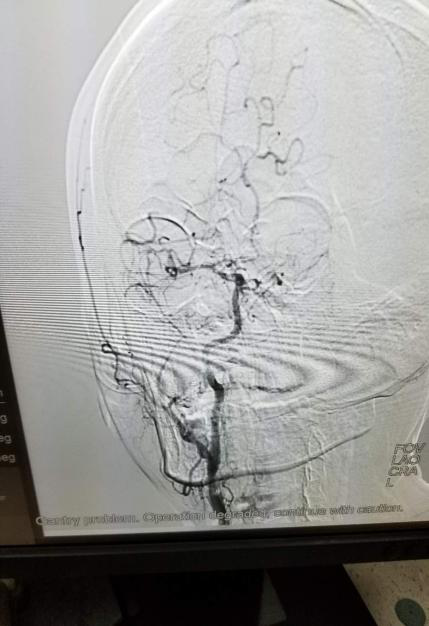

23:00 在局麻下成功股动脉穿刺,造影显示右侧颈内动脉起始处重度狭窄,大脑中动脉M1段急性闭塞,应用微导丝微导管技术,成功将取栓支架送入大脑中动脉闭塞处,后边负压吸引边牵拉取栓支架,取出数个血栓。

重复造影见血管腔恢复再通,00:00介入团队凭借深厚的介入功底及对脑血管疾病治疗的丰富临床经验,克服重重考验,在短时间内实现闭塞血管再通,血流灌注恢复。